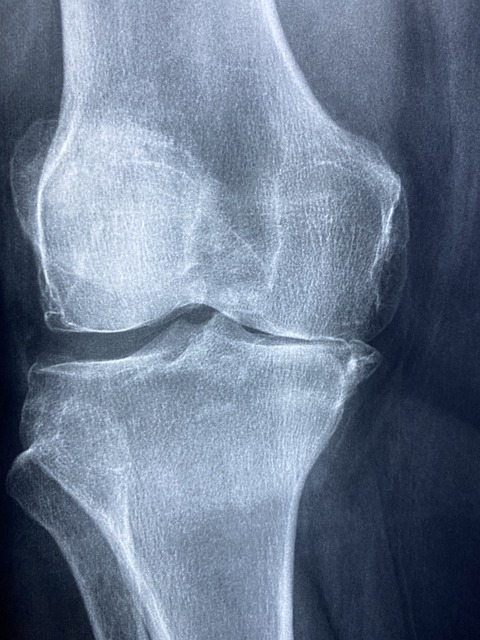

▶ 퇴행성 관절염은 관절, 특히 무릎, 엉덩이, 척추와 같이 체중을 지탱하는 관절에 영향을 미치는 질환입니다. 이는 관절의 연골이 파괴되어 통증, 뻣뻣함, 부기 및 운동 범위 감소를 초래하는 것이 특징입니다. 시간이 지남에 따라 골관절염은 악화될 수 있으며 개인의 삶의 질에 심각한 영향을 미칠 수 있습니다.

퇴행성 관절염 발생 원인

▶ 노화: 골관절염은 노인에게 더 흔합니다.

▶ 유전 요인: 특정 유전적 요인으로 인해 골관절염에 걸리기 쉽습니다.

▶ 관절 부상: 이전에 관절에 부상을 입었다면 골관절염 발병 위험이 높아질 수 있습니다.

▶ 비만: 과도한 체중은 관절에 추가적인 스트레스를 가해 골관절염의 위험을 증가시키며, 특히 무릎이나 엉덩이와 같이 체중을 지탱하는 관절에서 더욱 그렇습니다.

▶ 관절 과사용: 특정 직업이나 스포츠 활동 등 관절에 반복적인 스트레스가 가해지면 골관절염이 발생할 수 있습니다.